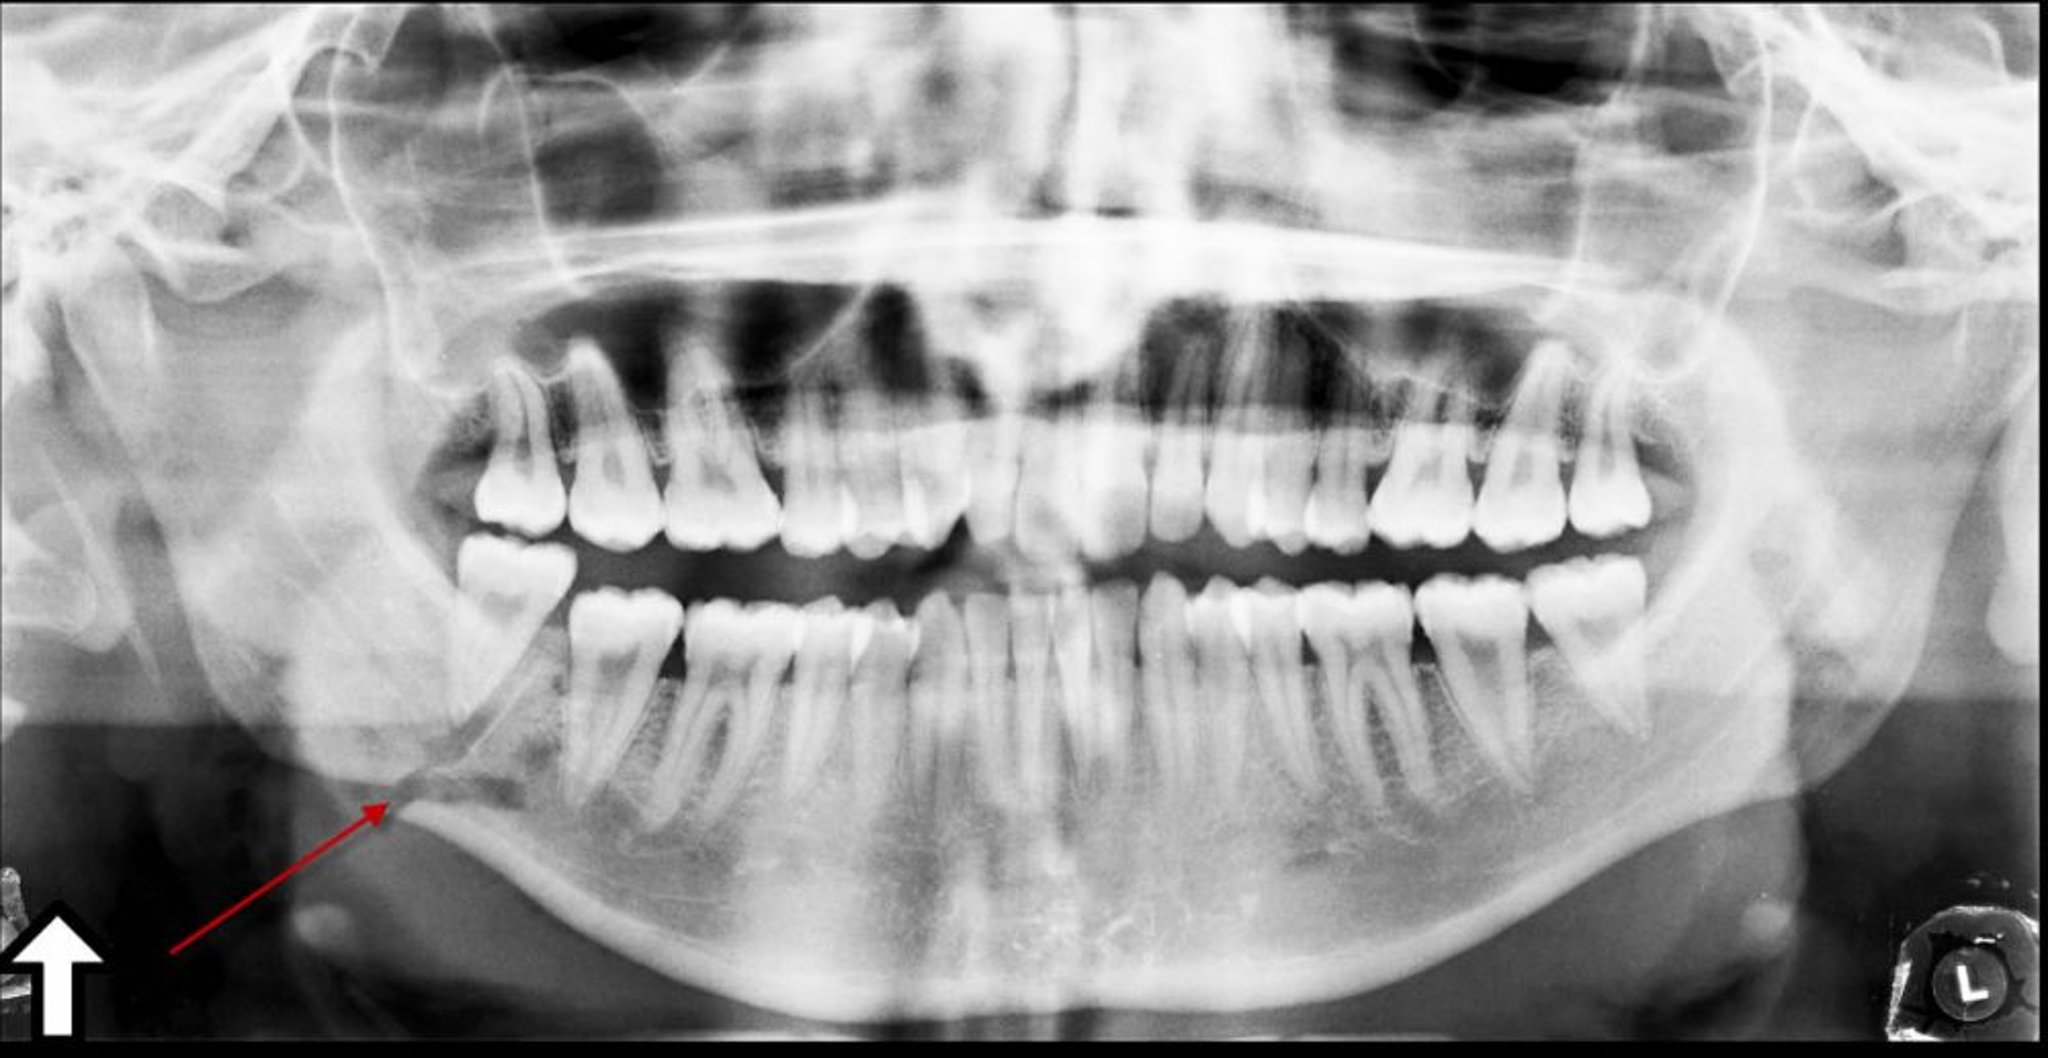

Gãy góc xương hàm dưới

Hình ảnh chụp X-quang toàn cảnh này cho thấy một vết lồi lõm (mũi tên) ở góc xương hàm dưới, cho thấy một vết gãy.